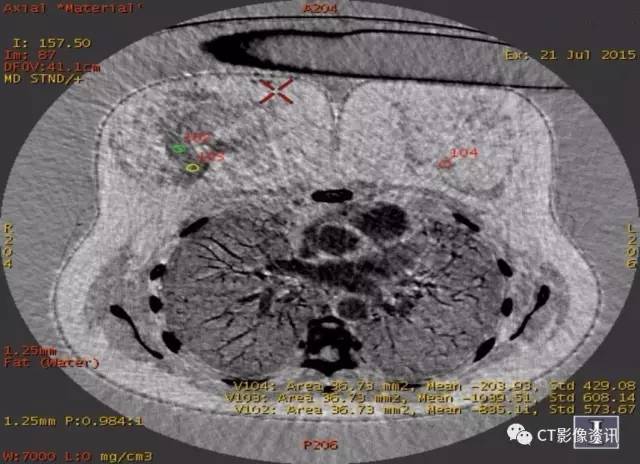

基物质定量分析,碘基/脂肪基

病侧腺体内的碘含量高于正常腺体,脂肪含量明显低于正常腺体。